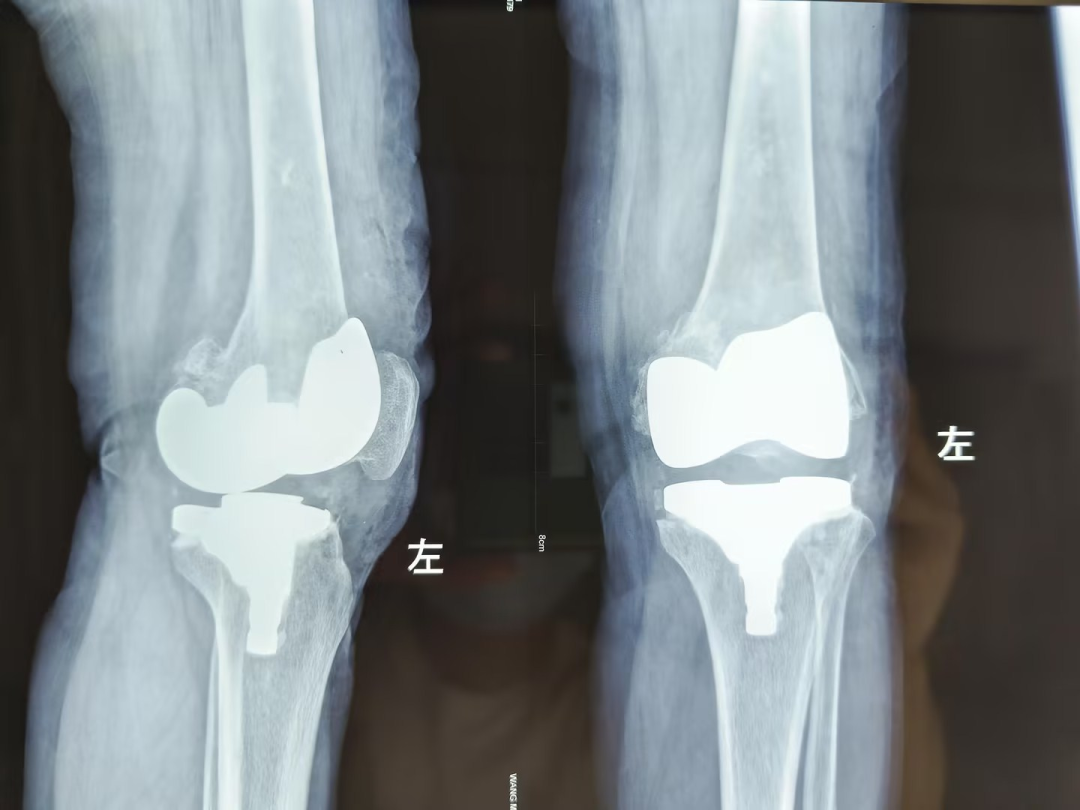

在创伤骨科住院后,经安勇主任医师团队诊断,王先生为双侧膝关节骨性关节炎,双侧膝关节内翻畸形。结合病史及影像学检查,考虑行双侧膝关节置换手术,因王先生左膝疼痛较右膝疼痛明显,所以先行左膝关节置换手术,术后10天,患者左膝疼痛减轻后,再行右膝膝关节置换手术。手术取得圆满成功,解除了王先生十余年的病痛。